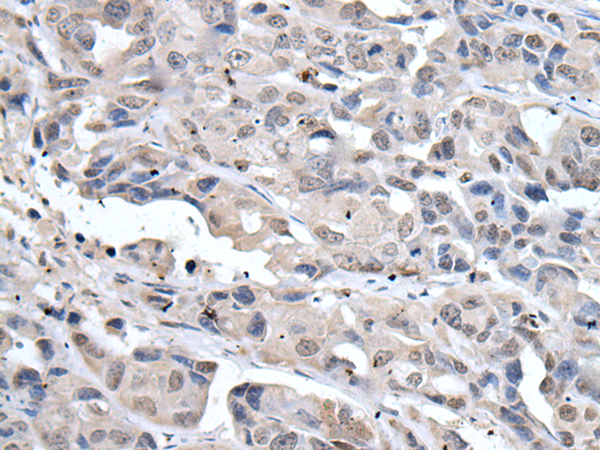

分类: 科研抗体货号: P08618别名: HPH2; PHD2; SM20; ECYT3; HALAH; HPH-2; HIFPH2; ZMYND6; C1orf12; HIF-PH2应用: IHC反应种属: Human, Mouse, Rat